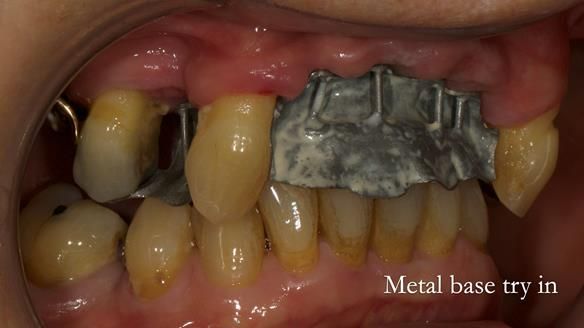

In this edition, I present the removable partial denture treatment for Jean, an 80-year-old woman with a sore mouth caused by a soft tissue-supported 'gum stripper' acrylic denture and a clenching habit. Below, I outline the step-by-step process of her treatment. It wasn't straightforward; I had to remake the denture after it fractured to achieve a satisfactory result. Each patient is unique, and sometimes a new RPD serves as a prototype. Occasionally, I need to make adjustments, learn from any mistakes, and refine the design to get it right.